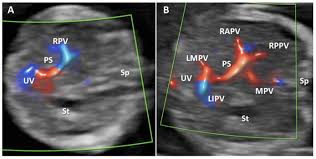

대동맥 및 기타 혈관

• 복부 대동맥류(AAA)

• 혈관 협착, 혈전 형성